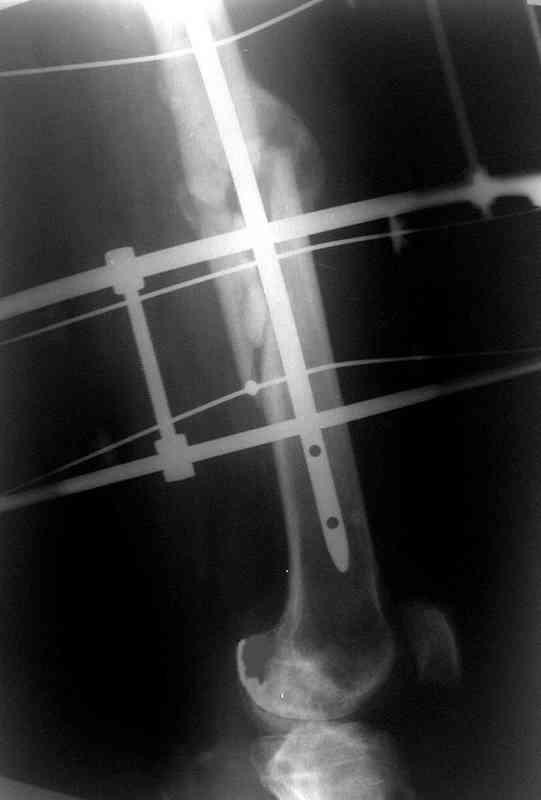

по его наружной поверхности послеоперационный рубец - рана зажила первичным натяжением. При измерении длины бедер обнаружено укорочение левого бедра на 4,5 см. На рентгенограммах этого бедра: ось конечности правильная, отмечается захождение основных костных фрагментов по длине, проксимальный конец штифта выступает слишком медиально и высоко относительно большого вертела, периостальная мозоль незначительна.22.12 - через 6 месяцев после операции, произведенной в ЦРБ, нами по поводу замедленно консолидирующего перелома левой бедренной кости с ее абсолютным укорочением под наркозом произведена операция: удаление штифта, закрытый блокирующий интрамедуллярный остеосинтез перелома левого бедра штифтом без рассверливания (UFN) длиной 40 см, диаметром 10 мм с блокированием только проксимальных отверстий (динамический остеосинтез). Наложен аппарат Илизарова на 4 полукольцах с целью удлинения укороченного бедра. Послеоперационное течение без особенностей. Ежедневно осуществляли дистракцию отломков на 1 мм. Через 3 недели после операции больной выпи-сан на амбулаторное лечение с продолжением дистракции отломков. В течение 1,5

месяцев дистракции укорочение левого бедра удалось полностью устранить. 22.02.00, т.е. через 2 месяца после повторного остеосинтеза, больному произведено дистальное блокирование штифта двумя винтами и демонтирован аппарат Илизарова. В течение 2 недель после операции больной ходил с помощью костылей, потом 2 недели с тростью. Опороспособность и функция оперированной конечности полностью восстановились через 4 недели после операции.